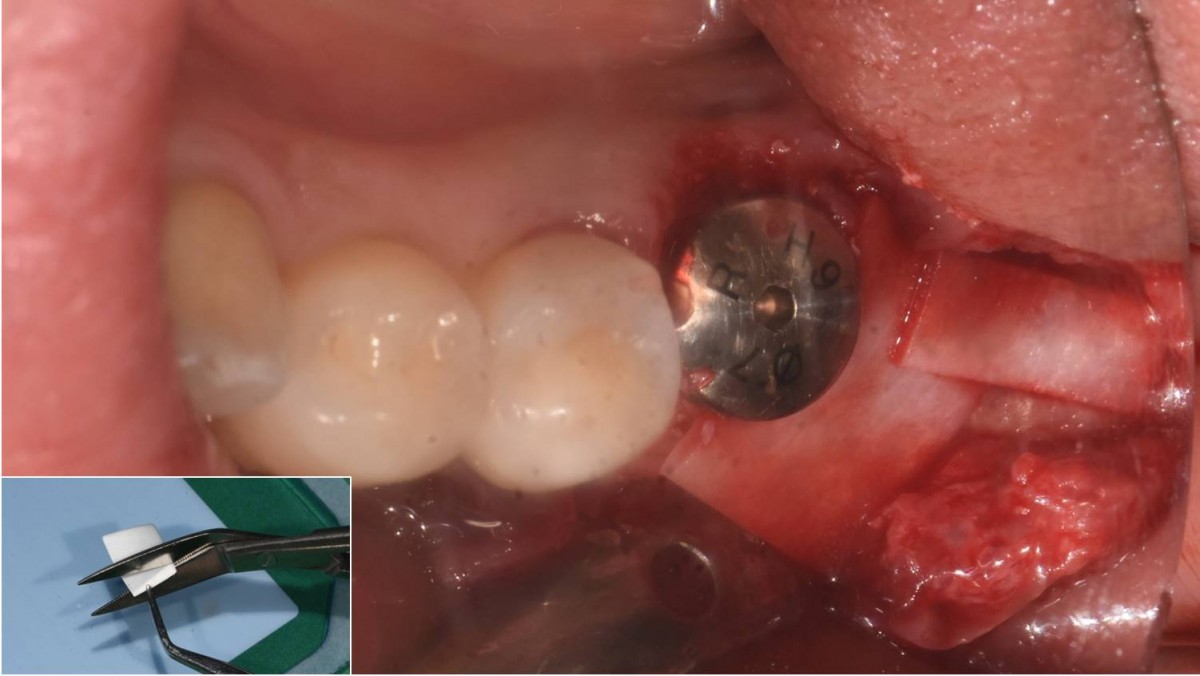

A 55-year-old female patient had

bilateral problems in both jaws.

It was decided to proceed with implant-supported restoration in the left molar part first.

She had been taking hypertension medication for a long time.